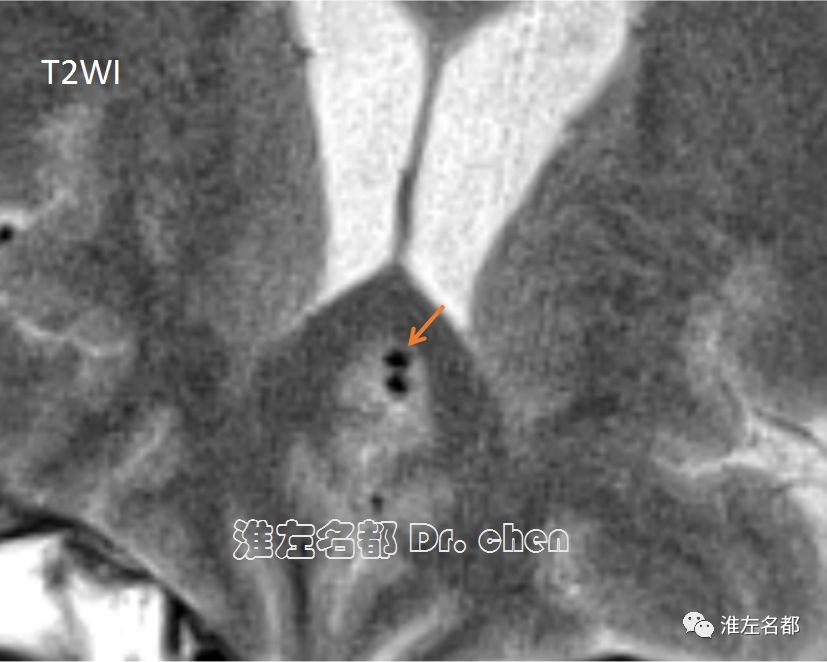

△发病3个月管壁高分辨MRI之T2WI:原左侧大脑前动脉A2段夹层壁内血肿已吸收,管腔恢复正常(橙箭)